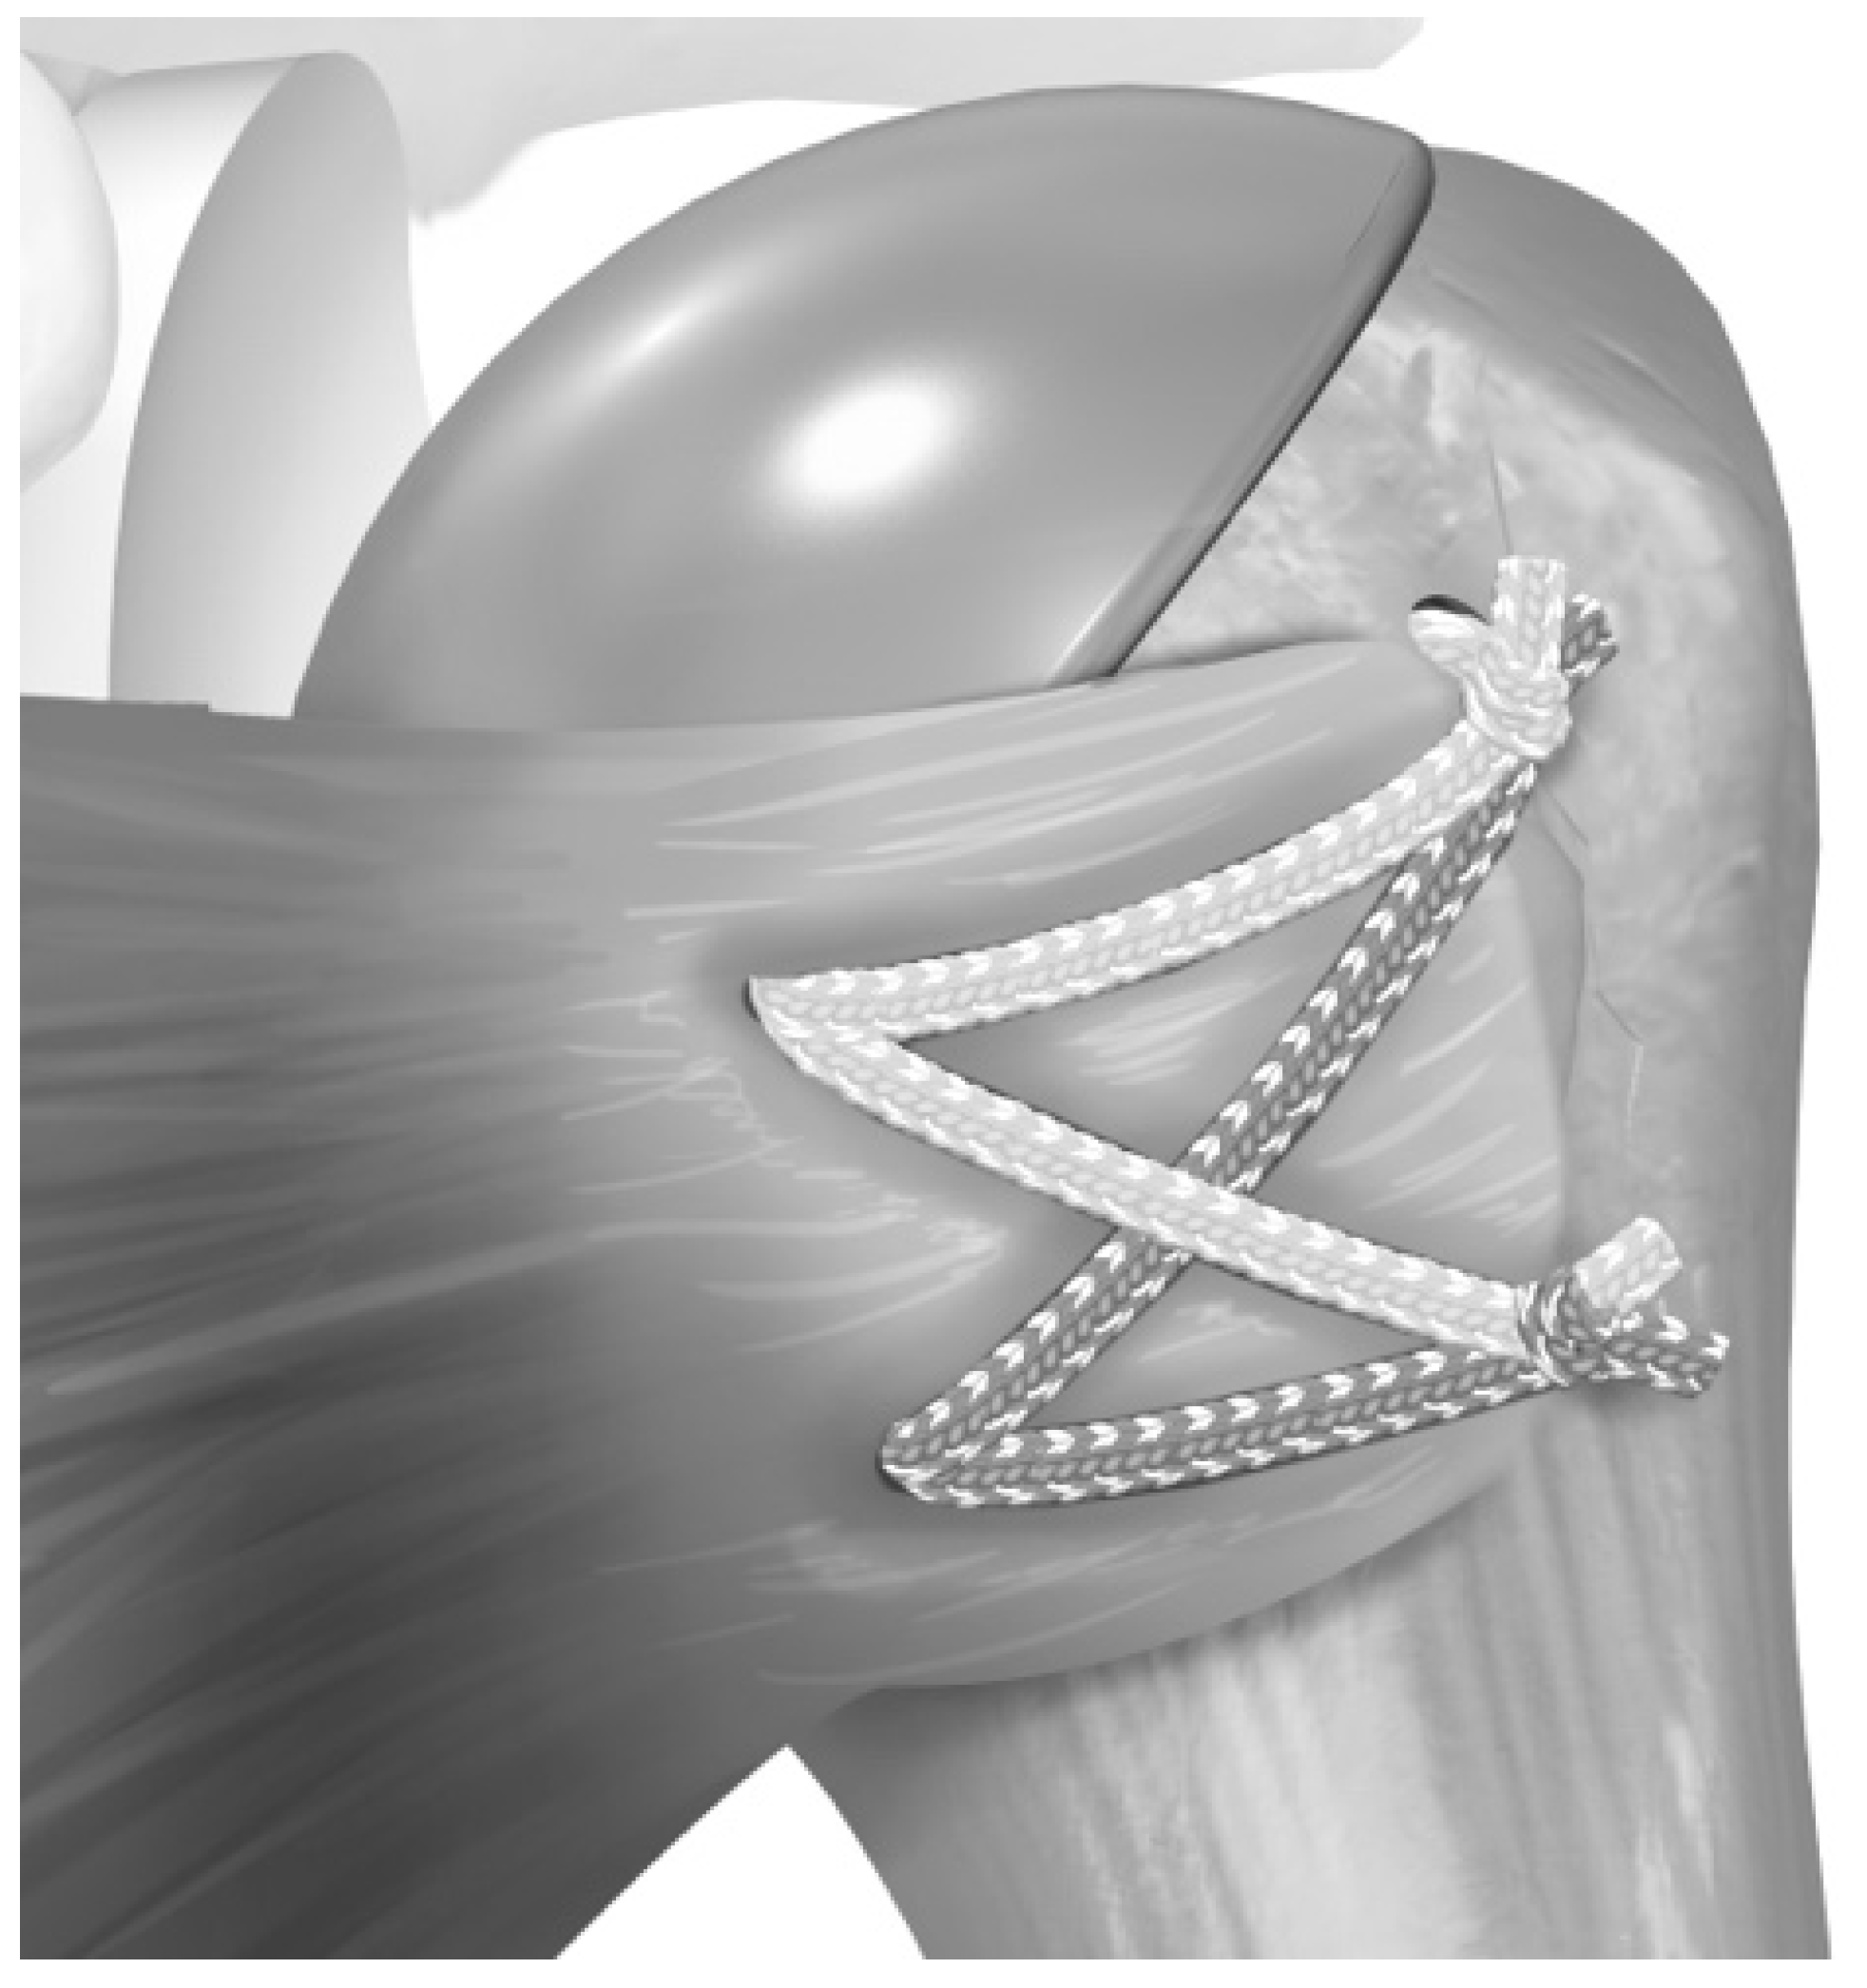

2.2. Surgical Technique

- Denard, P.J.; Noyes, M.P.; Lädermann, A. A Tensionable Method for Subscapularis Repair after Shoulder Arthroplasty. JSES Open Access 2018, 2, 205–210. [Google Scholar] [CrossRef]

- Heckman, D.S.; Hoover, S.A.; Weinhold, P.S.; Spang, J.T.; Creighton, R.A. Repair of Lesser Tuberosity Osteotomy for Shoulder Arthroplasty: Biomechanical Evaluation of the Backpack and Dual Row Techniques. J. Shoulder Elb. Surg. 2011, 20, 491–496. [Google Scholar] [CrossRef]

- Lederman, E.; Streit, J.; Idoine, J.; Shishani, Y.; Gobezie, R. Biomechanical Study of a Subscapularis Repair Technique for Total Shoulder Arthroplasty. Orthopedics 2016, 39, e937–e943. [Google Scholar] [CrossRef]